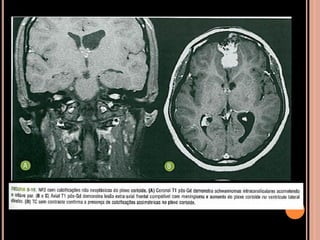

Área de vacuolização de mielina

 Focos hiperintensos em T2 e no FLAIR em núcleos

da base, cápsula interna, tronco encefálico e

cerebelo;

 Mais comum no globo pálido, geralmente bilateral;

Vacuolização de mielina

 Aparecimento geralmente aos 3 anos  aumenta

até os 12 anos  tendência a regredir;

 Raro observar após os 20 anos de idade;

 Calcificação assimétrica de plexo corióide

CALCIFICAÇÕES NÃO NEOPLÁSICAS DO PLEXO

CORIÓIDE

VL, assimétrica ou unilateral;

Usualmente não apresenta crescimento em exames

seriados;

TC